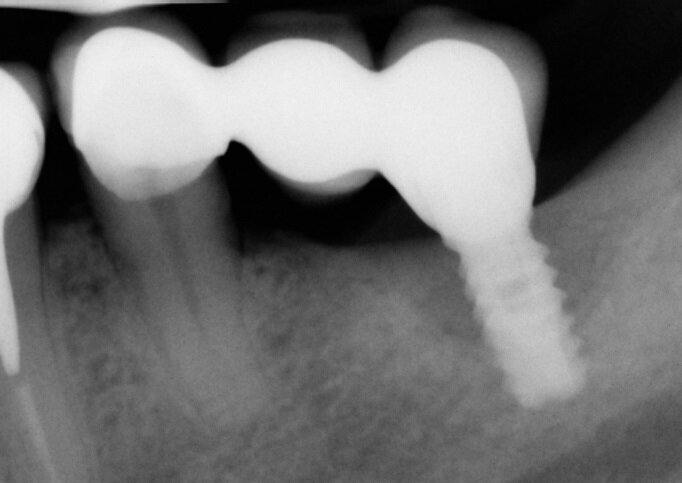

A termine del trattamento descritto in precedenza da un punto di vista clinico abbiamo ottenuto un ripristino dei parametri di salute dell’impianto ovvero la scomparsa del sanguinamento dell’edema e della purulenza, in oltre si è verificata una riepitelizzazione dei tessuti molli limitrofi l’impianto. Da un punto di vista radiografico abbiamo ottenuto la neoformazione di osso attorno alle spire dell’impianto (con relativo aumento della stabilità) che a inizio terapia era da considerarsi potenzialmente come perso. La radiografia a 60 gg prima ed a 1 anno mostrano quanto prima descritto, ovvero un ripopolamento di componenti cellulari ossei sull’impianto con un recupero di 3 spire implantari (Figg. 7-9).